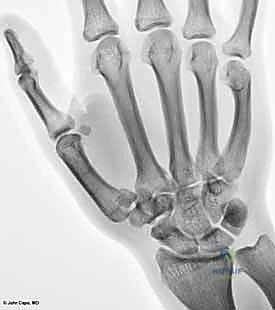

البنية العظمية للمفصل (The Bony Anatomy)

يتكون هذا المفصل من التقاء قاعدة عظم المشط الأول للإبهام (First Metacarpal Bone) مع العظم المربعي (Trapezium) الموجود في صف عظام الرسغ. يُصنف هذا المفصل من الناحية التشريحية على أنه "مفصل سرجي حقيقي" (Saddle Joint). هذا يعني أن الأسطح المفصلية لكلا العظمين تتخذ شكلاً مقعراً في اتجاه ومحدباً في الاتجاه الآخر، مما يسمح لها بالتشابك التام.

2. التصوير بالأشعة السينية (X-rays)

هي الأداة التشخيصية الأولى والأهم. يتم إجراء صور أشعة بزوايا محددة جداً:

* المنظور الأمامي الخلفي (AP View).

* المنظور الجانبي الحقيقي (True Lateral View): وهو ضروري جداً لتقييم مدى الخلع أو الانزياح في المفصل.

* منظور روبرت (Robert's View): وضعية خاصة للأشعة السينية تظهر مفصل الإبهام الرسغي السنعي بوضوح تام وتكشف عن أدق التفاصيل في كسور بينيت ورولاندو.